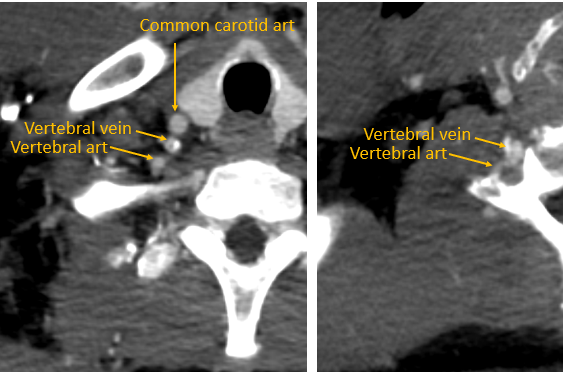

5/ If uncertain, check steep oblique or lateral view – the VV veers posteriorly towards the spine as you can see in this different patient. The IJ is an anterior structure that is usually relatively in-line with SVC.

4/ From IJ/SC/BC vein confluence, the VV veers posteriorly to follow the vertebral art into the transverse foramen, where it becomes diminutive and more plexus-like. On frontal view can look like a small IJ. Recognize this vein, and never think to put in a snare to stick down on!